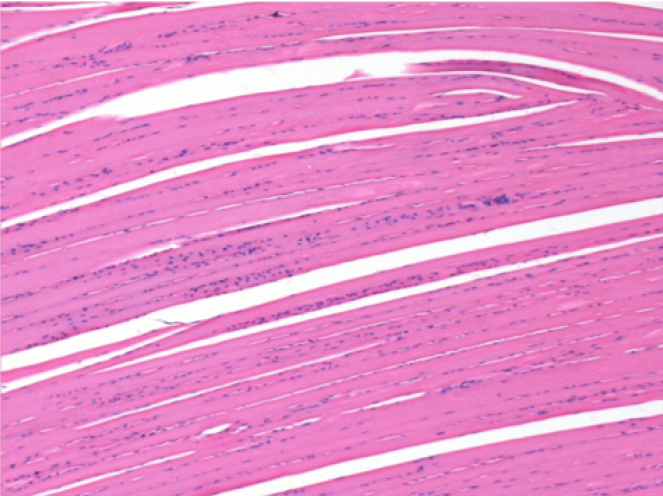

1 month after Endopeel Injection 0.1ml in the right pretibial muscle.

What is seen in black on the pictures is not a necrosis like could imagine some scientifics !

In fact, 4 conclusions have to be taken in consideration